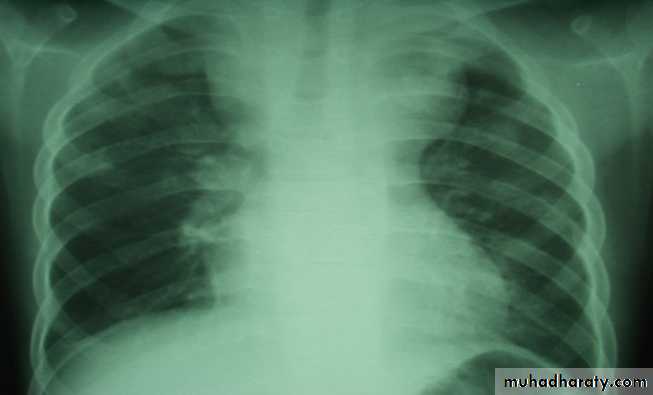

• INVESTIGATIONS:

• 1.CXR, CBP & E.S.R, lymhocytosis

• 2.Tuberculine -ve.

• 3.LN biopsy ( T.B Granuloma).

• 4.Aspiration of cold abscess & guinea pig inoculation

• 5.Smears of sinus for AFB.